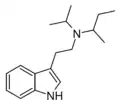

| iPsBT | artificial | H | CH(CH3)2 | CH(CH3)CH2CH3 | N-isopropyl-N-sec-butyltryptamine | |